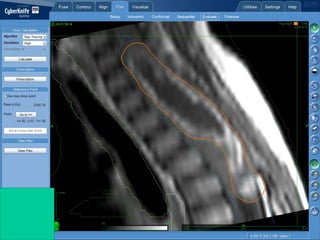

ASTROCITOMA ANAPLASICO

INTRADURAL INTRAMEDULAR

Consultó con 4 AÑOS, ahora con 9 años

INOPERABLE

2 ESQUEMAS DE QUIMIOTERAPÍA

PROGRESION DE LA ENFERMEDAD

PARAPARESIA

Respuesta al tratamiento

ANTES DESPUES

5 meses posCyberknife

50 meses posCyberknife